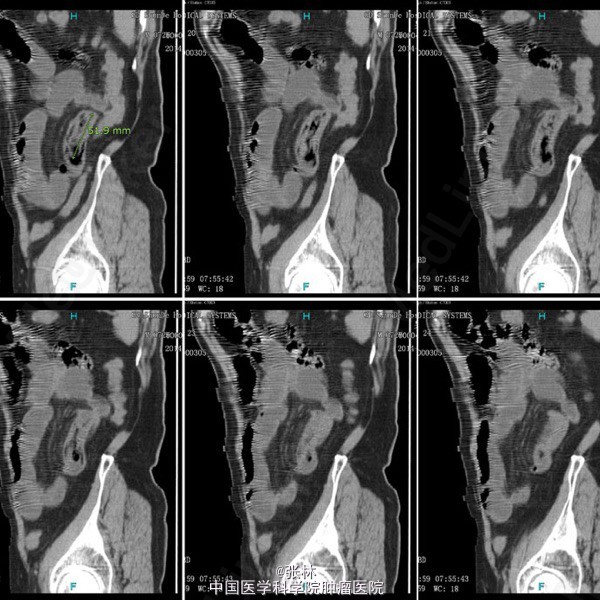

男性,72岁。 主诉:突发腹痛、腹胀伴呕吐1天。 现病史:患者1天前无诱因感全腹部疼痛,呈阵发性绞痛,无放射痛,疼痛开始不剧,伴有畏寒,呕吐胃内容物1次,量约30ml。遂到我院门诊就诊,考虑为急性胃肠炎,予抗炎、解痉护胃等支持治疗,症状未见好转,并进行性加重而入住我科。 专科检查:全腹稍胀,未见肠型及蠕动波,无上腹搏动。腹软,中下轻压痛,无反跳痛。全腹未及肿块,肠鸣音活跃,7次/分。 术中所见:探查见异物位于回肠距回盲部约50cm,大小约8*3*2cm,堵塞肠管,近端肠管充血水肿明显,肠管扩张最大处直径约8cm,未见浆膜层破裂损伤等,系膜无扭转,有少许渗液,探查全部小肠未及肿物腹腔内可见中等量黄色积液,稍浑浊,网膜及腹膜有少量脓苔。洗净腹腔内积液,于肿物边缘对肠系膜缘纵行切开约2cm,取出异物,为半个大小约8*3*2cm的冬菇。